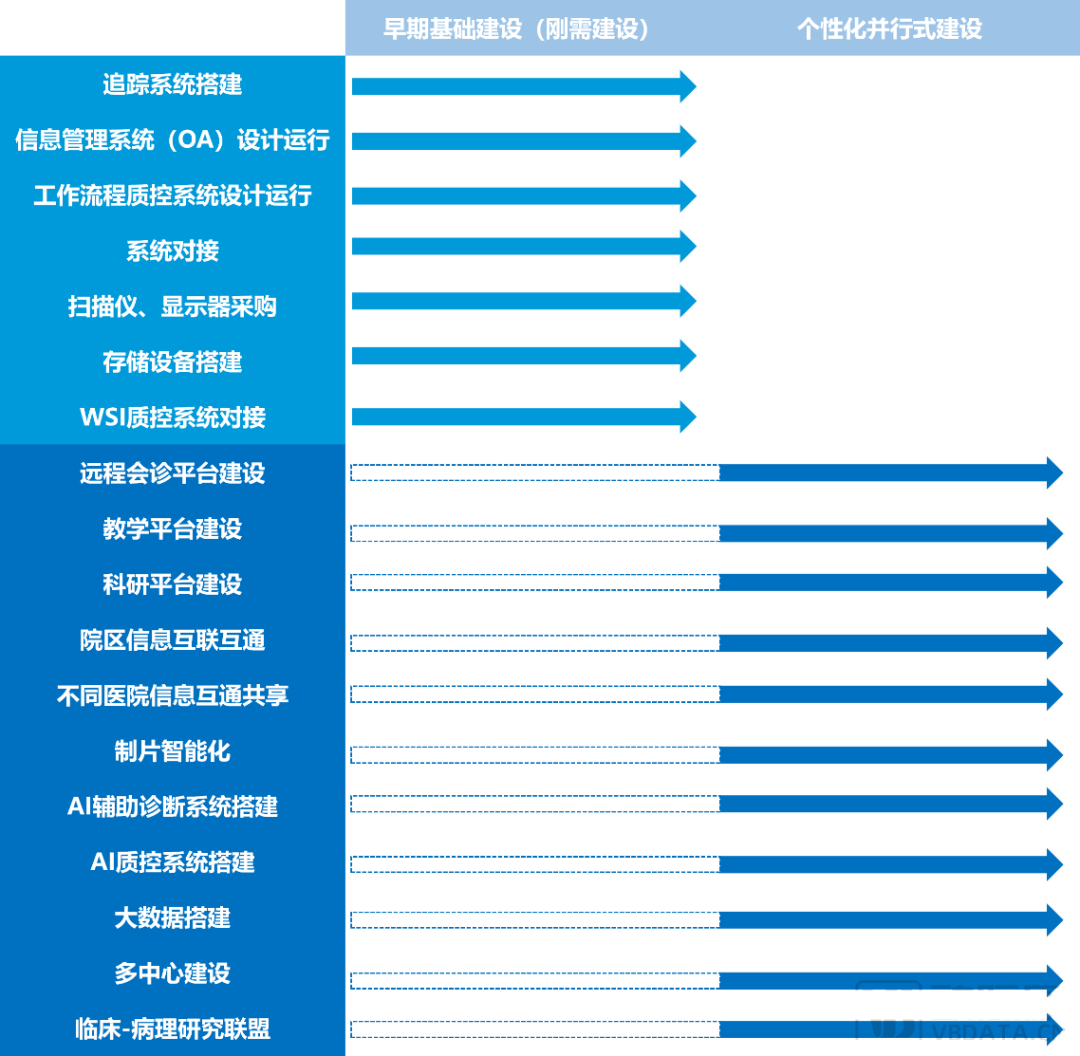

数字化智慧病理科建设指南:分级建设是核心主旨

分级建设方案